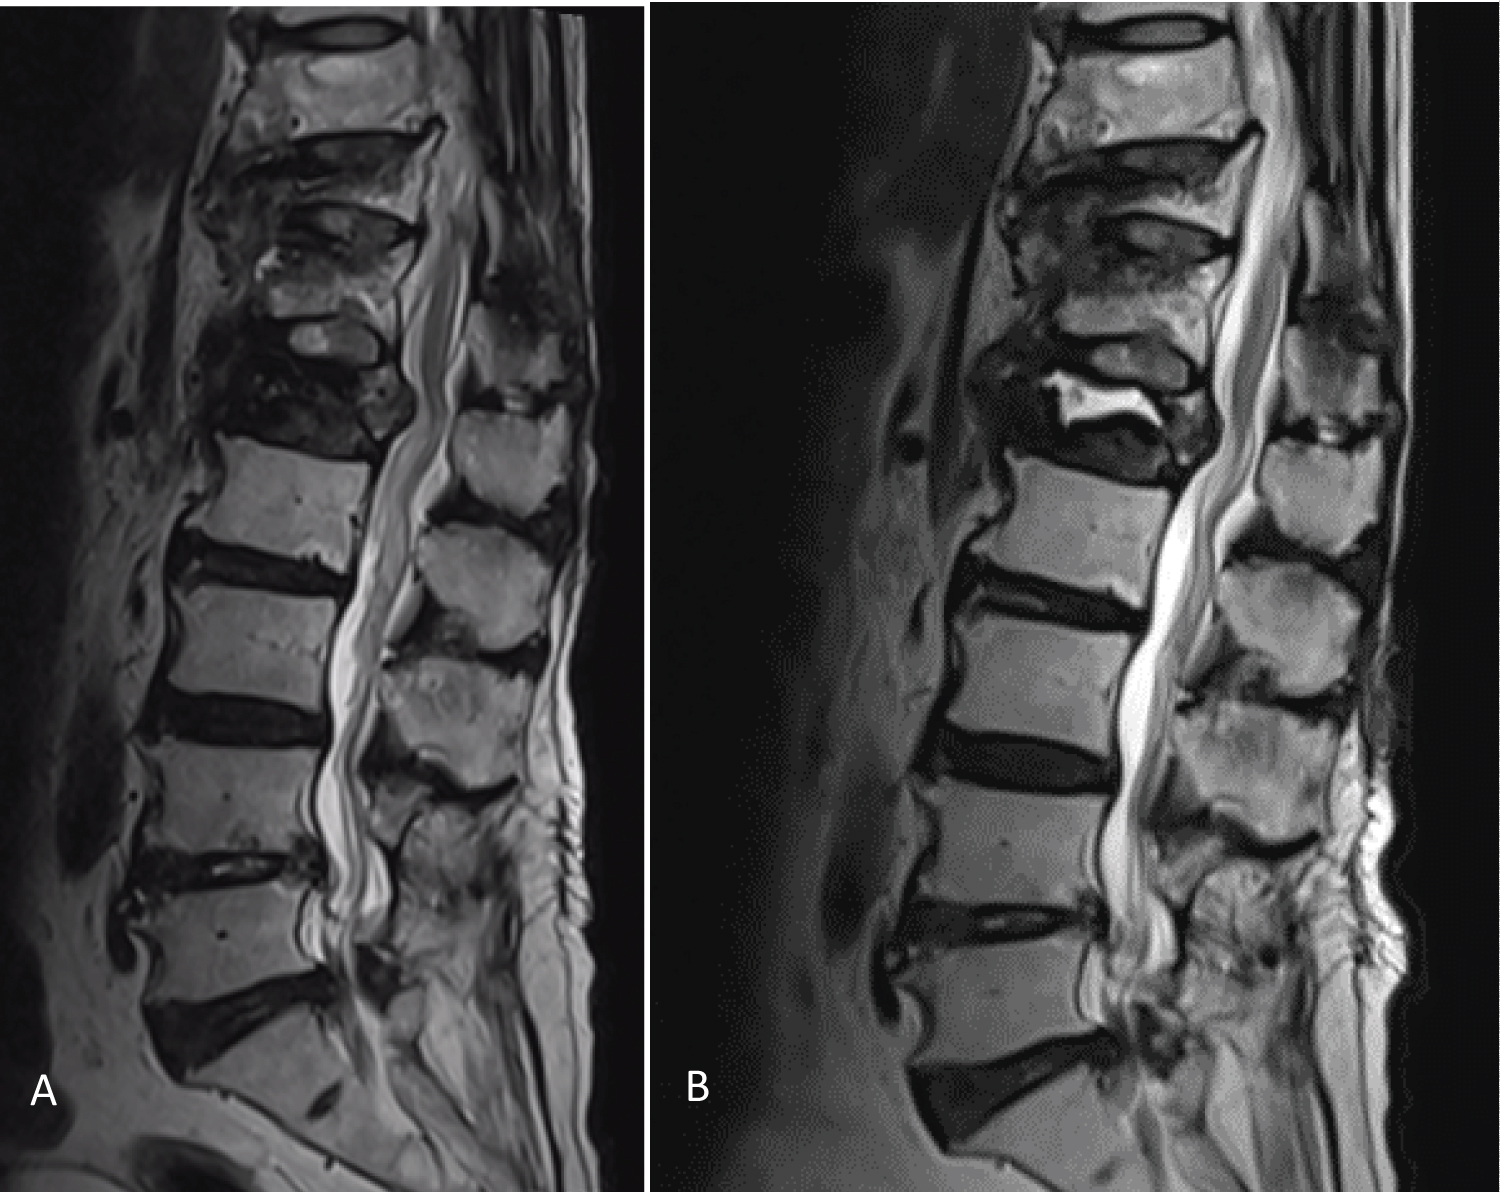

Figure 1: Preoperative magnetic resonance imaging.

Initial magnetic resonance imaging showed burst fracture over T11, T12, and L1 vertebral bodies (A). 3 months later (B), T2-weighted image showed homogeneous hyperintensity at the anterior superior portion of the L1 vertebral body. The margin of the hyperintense area is well demarcated. Osteonecrosis is present. View Figure 1